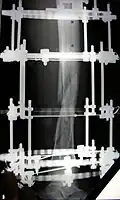

Процедура лечения открытого перелома большой и малой берцовой костей аппаратом Илизарова. Фотографии и рентгенограммы одного и того же пациента в течение курса лечения. Снимки 2 — 6 сделаны через четыре недели после перелома (две недели после наложения аппарата).

Рентгенограмма перелома и первоначальный внешний фиксатор, наложенный в течение 24 часов после поступления в больницу. -

Рентгенограмма места перелома сразу после наложения аппарата Илизарова -

Рентгенограмма места перелома (через два месяца после перелома), № 1 -

Рентгенограмма места перелома (через два месяца после перелома), № 2 -

Рентгенограмма места перелома (через три месяца после перелома), № 1. Костная мозоль образуется вокруг места перелома -

Рентгенограмма места перелома (через три месяца после перелома), № 2. Костная мозоль образуется вокруг места перелома -

Рентгенограмма места перелома (через четыре месяца после перелома)